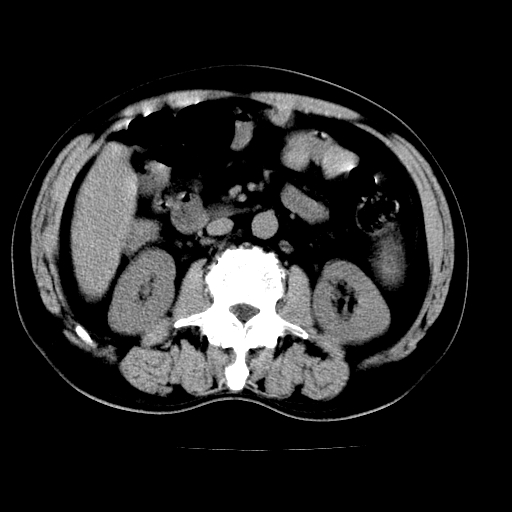

男,66岁,上腹部不适、黄染一周。彩超示:肝左叶占位,肝内胆管扩张,胆总管扩张,胆总管占位?

肝左叶不规则软组织肿块影,边缘不规整邻近肝实质受累分界不清;肝内胆管(左叶)明显扩张成“软藤状”,诊断:肝左叶胆管细胞癌。

肝左叶占位性病变,并胆管扩张,符合胆管细胞癌ct表现,门脉左支受累,左肾囊肿。窗宽太窄了,其他的看不清

左叶胆管细胞癌累及胆总管,门脉左支受侵,慢性胆囊炎胆结石,左肾小囊肿

肝左叶不规则软组织肿块影,边缘不规整邻近肝实质受累分界不清;肝内胆管(左叶)明显扩张成“软藤状”,诊断:肝左叶胆管细胞癌。胆囊钙乳症。